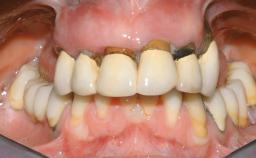

Immediate Loading of Eight Implants in the Maxilla and Six Implants in the Mandible and Final Restoration with Three-Unit and Four-Unit FDPs

Extensive scientific evidence has confirmed that immediately loaded implants with fixed full-arch provisional restorations can osseointegrate with success rates similar to conventionally or delayed loaded implants. A number of immediate-provisionalization techniques for edentulous jaws have been described. Some protocols differ when it comes to prefabricated provisional templates versus complete denture conversion; intrasurgical impressions versus direct relining; and cemented versus screw-retained provisional restorations. In this context, complete-denture conversion has been proposed for either intrasurgical impressions or direct relining. Another possibility is the utilization of a prefabricated provisional to be adapted either in the mouth (by direct relining) or in the laboratory (on a working model obtained from an intrasurgical impression).

Case Type Edentulous Maxilla

Bone Volume Horizontally and vertically sufficient Horizontally deficient Deficient vertically or deficient vertically AND horizontally